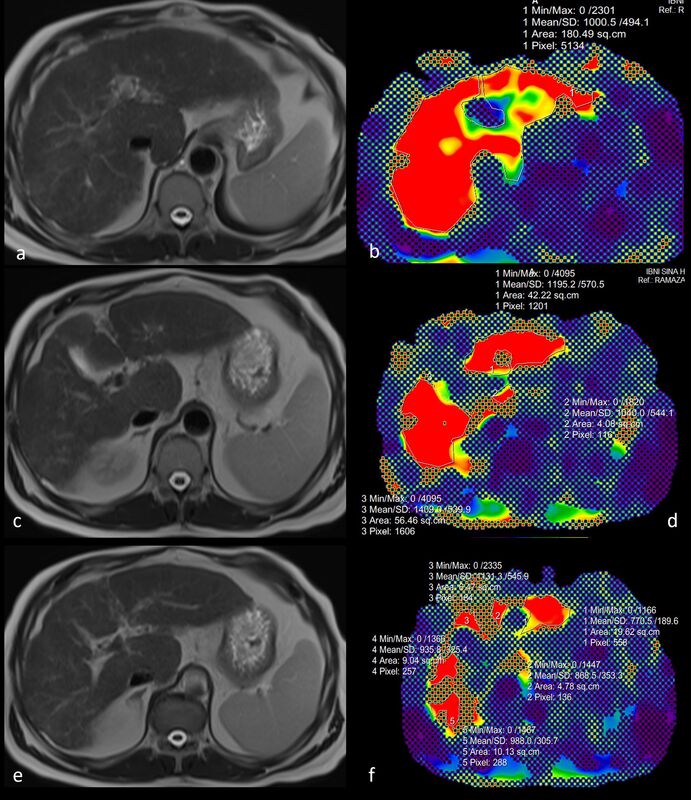

Figure 3

A 58-year-old male patient with grade 3 oesophageal varices at endoscopy and a diagnosis of cirrhosis secondary to non-alcoholic fatty liver disease. In measurements made from magnetic resonance elastography confidence maps (B, D, F), liver parenchymal stiffness per unit area was calculated as 10.7 kPa